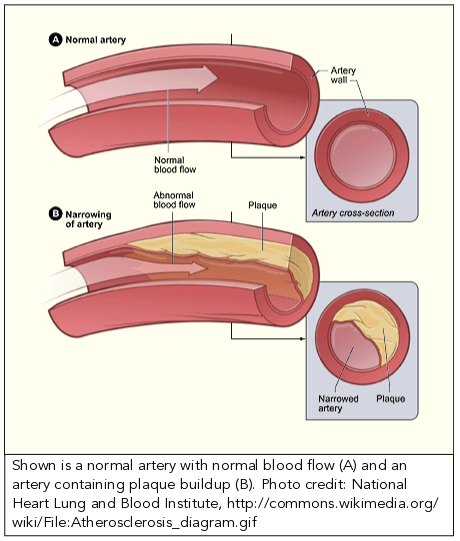

A typical blood vessel. ( a ) shows a normal artery with normal blood …

a deposit of plaque within the arterial wall

Albums showcases captivating images of a deposit of plaque within the arterial wall galleryz.online